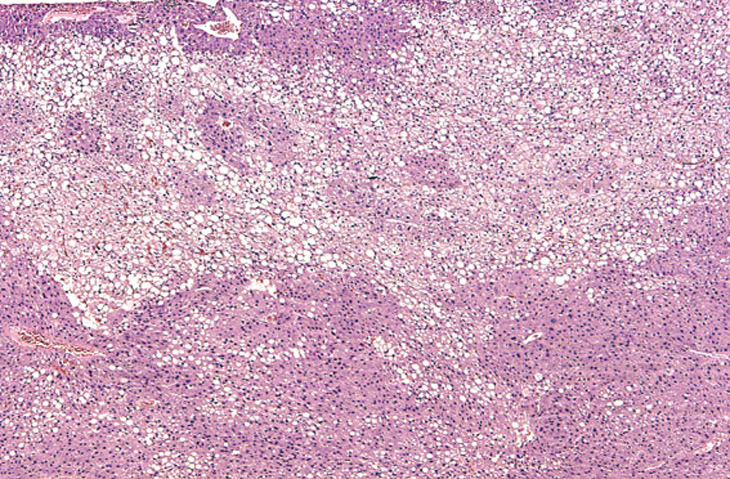

Large areas of fatty change without a distinct lobular pattern are present in this liver. The large, sharply delineated, clear vacuoles represent macrovesicular fat that has been dissolved during tissue processing. Deposition of fat in the hepatocyte cytoplasm often displaces the hepatocyte nucleus to the periphery of the cell.